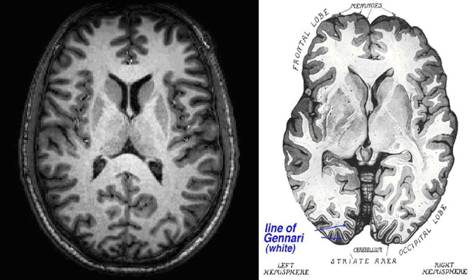

(a) (b)

Figure

4. (a) Horizontal structural MRI scan of the

brain. (b) Horizontal anatomical image of the brain showing the line of Gennari. It can be seen that (a) does not provide enough

information to locate the line of Gennari in the

scan.